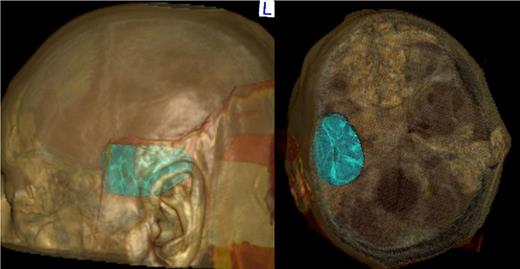

The brain CT scan was reconstructed using the program OsiriX, as shown in Fig. 1, so that it was possible to establish accurate cranial landmarks to guide the burr hole position.

After the patient was put in the proper position, guided by the 3D imaging, we were able to perform a single small incision and a single burr hole at the posterior aspect of the hematoma. The neuroendoscope (Storz–HOPKINS®–Forward–Oblique Telescope 30°) was positioned in a 45° direction, headed from the posterior limit of the hematoma to the media fossa floor, in a way that the whole hematoma could be visualized. With the neuroendoscope in place, the surgeon uses the other hand to hold a 7–9 gauge suctor. Then, both the suctor and the neuroendoscope are progressively inserted through the burr hole, following the natural corridor provided by the hematoma evacuation. After satisfactory hematoma evacuation, the camera was again placed to confirm hemostasis. If some level of hemorrhage emerges, irrigation with 0.9% saline is enough to stop bleeding. If bleeding persists, pieces of surgicel can be left in place. A small piece of Gelfoam is placed over the burr hole, and the wound is closed in layers.